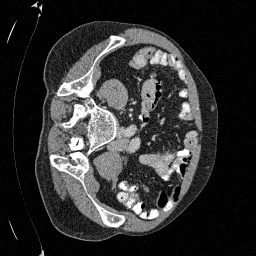

Training an NCSN on Abdomen CT - I

Figure 1: Some augmented example images from the training split.